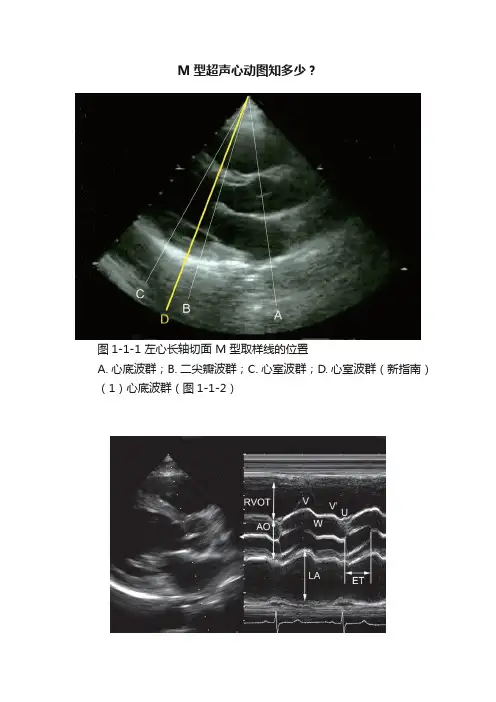

M型超声心动图知多少?图1-1-1 左心长轴切面 M 型取样线的位置A. 心底波群;B. 二尖瓣波群;C. 心室波群;D. 心室波群(新指南)(1)心底波群(图1-1-2)图1-1-2 心底波群RVOT:右室流出道;AO:主动脉;LA:左心房■胸骨旁左室长轴切面 M 型取样线置于主动脉瓣水平,与主动脉及左心房后壁垂直。

■从前到后为右室流出道、主动脉前壁、主动脉瓣、主动脉后壁、左房等结构。

■右室流出道紧贴于胸壁下,其前后径应在舒张末期(心电图 QRS 波起点,国内学者定为 R 波顶点)测量。

■主动脉根部 M 型曲线为两条平行的强回声,分别代表主动脉的前、后壁,主动脉根部内径为在舒张末期测量主动脉前壁回声前缘至后壁回声前缘的距离。

●在心动周期中主动脉根部曲线呈规律性变化,心脏收缩时,主动脉曲线上升形成主波( V 峰);心脏舒张时主动脉曲线逐渐下降形成W 点,P 波前曲线又稍向上活动形成重搏波(V’峰)。

U 波为曲线最低点,在心电图R 波之后。

●正常人主波幅度应当>10mm,重搏波清晰可见。

●主动脉硬化则运动曲线幅度降低,重搏波消失。

■主动脉瓣的 M 型曲线在舒张期表现为一条与主动脉壁平行的瓣叶关闭线,收缩期主动脉瓣开放,呈六边形盒样曲线。

●正常人瓣叶六边形盒样曲线回声纤细,前、后方细线分别代表主动脉右冠瓣和无冠瓣,盒的宽度相当于左室射血时间(ejection time,ET);盒的高度代表瓣叶的开放幅度,正常值>15mm。

■测量心电图 QRS 波起点至主动脉瓣开放点之间的时间间期为左心室射血前期(pre-ejection period,PEP)。

■左心房内径随心动周期而改变,在收缩末期(心电图 T 波结束)达最大,在舒张末期心房收缩达最小。

●左房前后径应在收缩末期测量主动脉后壁(左房前壁)回声前缘至左房后壁回声前缘的距离。

●实际操作时还要注意取样线尽量与左房壁垂直,以保证测量的精确性。